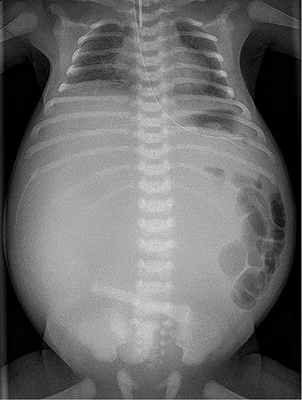

Для диагностики такого состояния врачи проводят обыкновенное рентгенологическое исследование органов брюшины. Такое исследование показывает аномальное расширение петель тонкой кишки, а также нехватку воздуха в ободочной и прямой кишке. У 10% пациентов еюноилеальная атрезия сочетается с муковисцидозом.

Еюноилеальная атрезия – незавершенное формирование части тонкой кишки. Диагноз устанавливают на основе результатов рентгенографии брюшной полости. Лечение подразумевает проведение восстановительной операции.

Диагностика еюноилеальной атрезии

Рентгеноскопическое исследование органов брюшной полости

Проводят обычный рентгенографию органов брюшной полости, который может обнаружить расширенные петли тонкой кишки с воздушно-жидкостным наполнением и недостаток воздуха в ободочной и прямой кишке. Ирригография позволяет диагностировать микроколон (в связи с тем, что данный отдел кишечника не задействован).